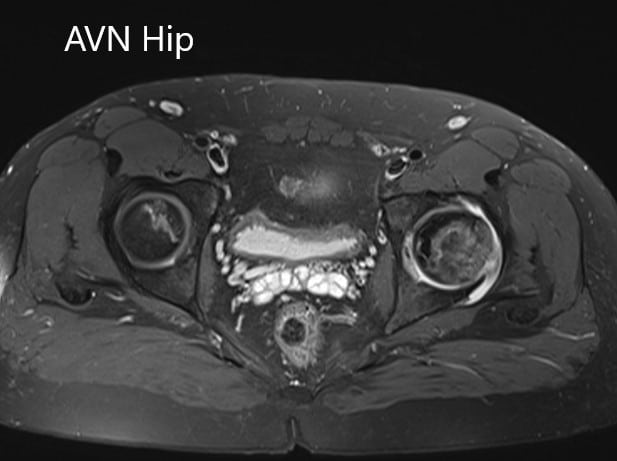

Imaging studies obtained in the form of an X-Ray suggested sclerosis of the left head of the femur. There were marked acetabulum changes. An MRI was further obtained suggesting avascular necrosis of the superior lateral head of the femur with changes in the acetabulum. There was marked hypointense areas on both T1WI and T2WIs.

T1WI coronal section of MRI showing AVN hip.

T2WI coronal section of MRI showing AVN hip.

Axial sections of the T1WI and T2WI of MRI.